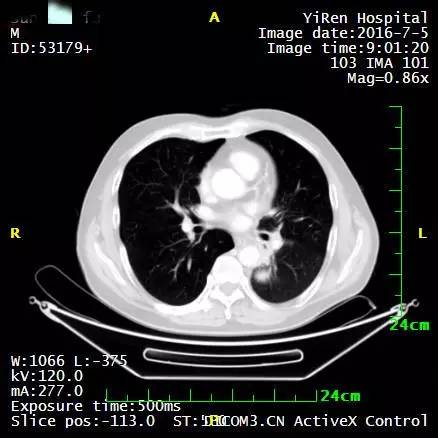

2、患者男性,64岁,小细胞肺癌

2016年3月,王先生因咳嗽加重就诊于当地医院,支气管镜病理检查提示:考虑小细胞癌的可能性大。

化疗一周期,病情无改善症状加重。

2016年4月,王先生接受了A45治疗,一个月后复查,病灶明显缩小,2016年7月复查,病灶进一步缩小,由于A45治疗具有明显的远观效应,能够激发自身的免疫系统,长期有效的消灭体内肿瘤,2016年12月,王先生肺部病灶几乎全部消失。

治疗前

治疗后

治疗后两个月

治疗后7个月

目前王先生态势良好,没有任何复发迹象。